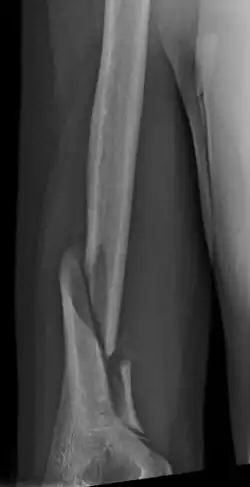

Holstein–Lewis fracture at 5 weeks post fracture | |

A Holstein–Lewis fracture is a fracture of the distal third of the humerus resulting in entrapment of the radial nerve.